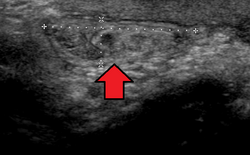

Ultrasound showing an inguinal hernia

By far the most common hernias (up to 75% of all abdominal hernias) are inguinal hernias, which are further divided into the more common indirect inguinal hernia (2/3, depicted here), in which the inguinal canal is entered via a congenital weakness at its entrance (the internal inguinal ring), and the direct inguinal hernia type (1/3), where the hernia contents push through a weak spot in the back wall of the inguinal canal. An indirect inguinal hernia and a direct inguinal hernia can be distinguished by their positioning in relation to the inferior epigastric vessels. An indirect hernia is situated laterally to these vessels, whereas a direct hernia is positioned medially to them. Inguinal hernias are the most common type of hernia in both men and women. In some selected cases, they may require surgery.

In the diagnosis of abdominal hernias, imaging is the principal means of detecting internal diaphragmatic and other nonpalpable or unsuspected hernias. Multidetector CT (MDCT) can show with precision the anatomic site of the hernia sac, the contents of the sac, and any complications. MDCT also offers clear detail of the abdominal wall allowing wall hernias to be identified accurately.[19]